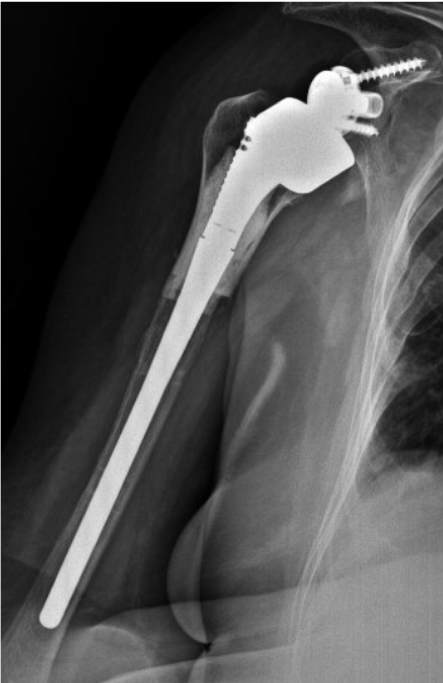

Post-op

Implantation of the LINK Embrace with hybrid fixation

- Modular Stem, L 165 mm, uncemented, combined with

- Proximal Body for maximum intra-op adaptability and stable proximal humerus, with allograft, cemented

- Eccentric PE-Gleno-sphere with 39 mm diameter and CoCr Reverse Insert with a 20° inclination

Result

- Second cultures (-)

- Good postoperative evolution

- No wound problems

6 months follow-up:

- No pain

- Active flexion: 70º

- Limited IR-ER